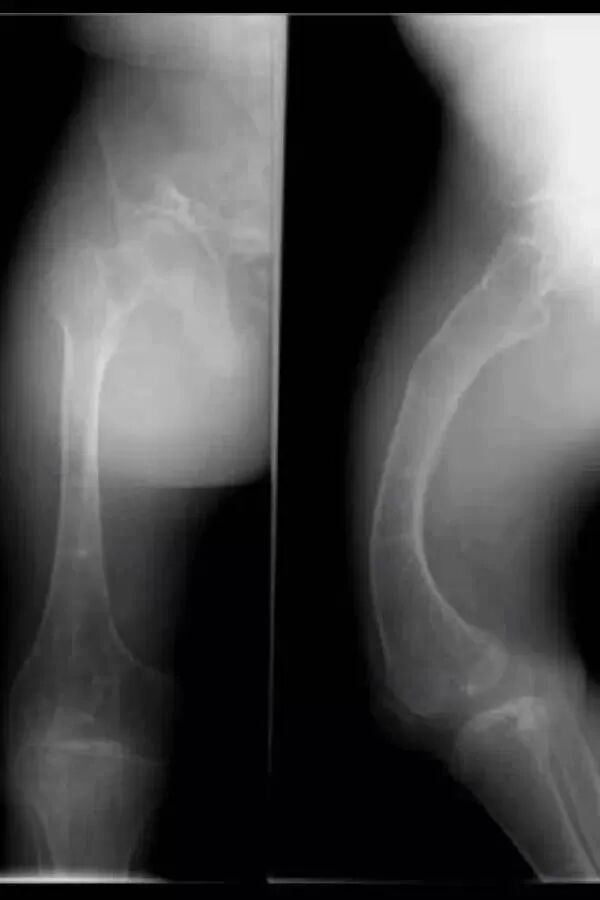

入院检查:患者男性,16岁,因“外伤致右大腿肿痛伴活动受限2天”;体查:平时坐轮椅生活,身高: 132cm,体重: 43kg,蓝巩膜,双下肢弯曲畸形,X形腿右下肢石膏固定,右大腿稍肿胀,压痛,可及骨擦感。辅查:本院X线及CT(见图一):右股骨干下段骨折,骨质疏松,双下肢弯曲畸形,胸片及ECG无明显异常;其他:既往史无特殊,父母及1兄弟均无遗传病史。

图一:入院X线及CT

入院诊断:1.右侧股骨干下段骨折伴双下肢畸形2.成骨不全症 3.继发性骨质疏松